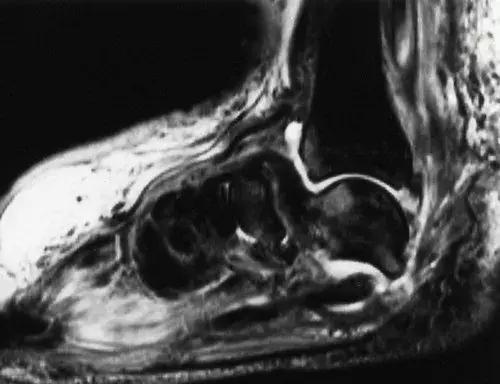

图22:52岁糖尿病男性,舟骨-跖骨关节的神经病理性破坏。侧位X线片显示舟骨的破坏吸收。神经性骨关节病通常更早涉及脚的内侧,比外侧柱更频繁。